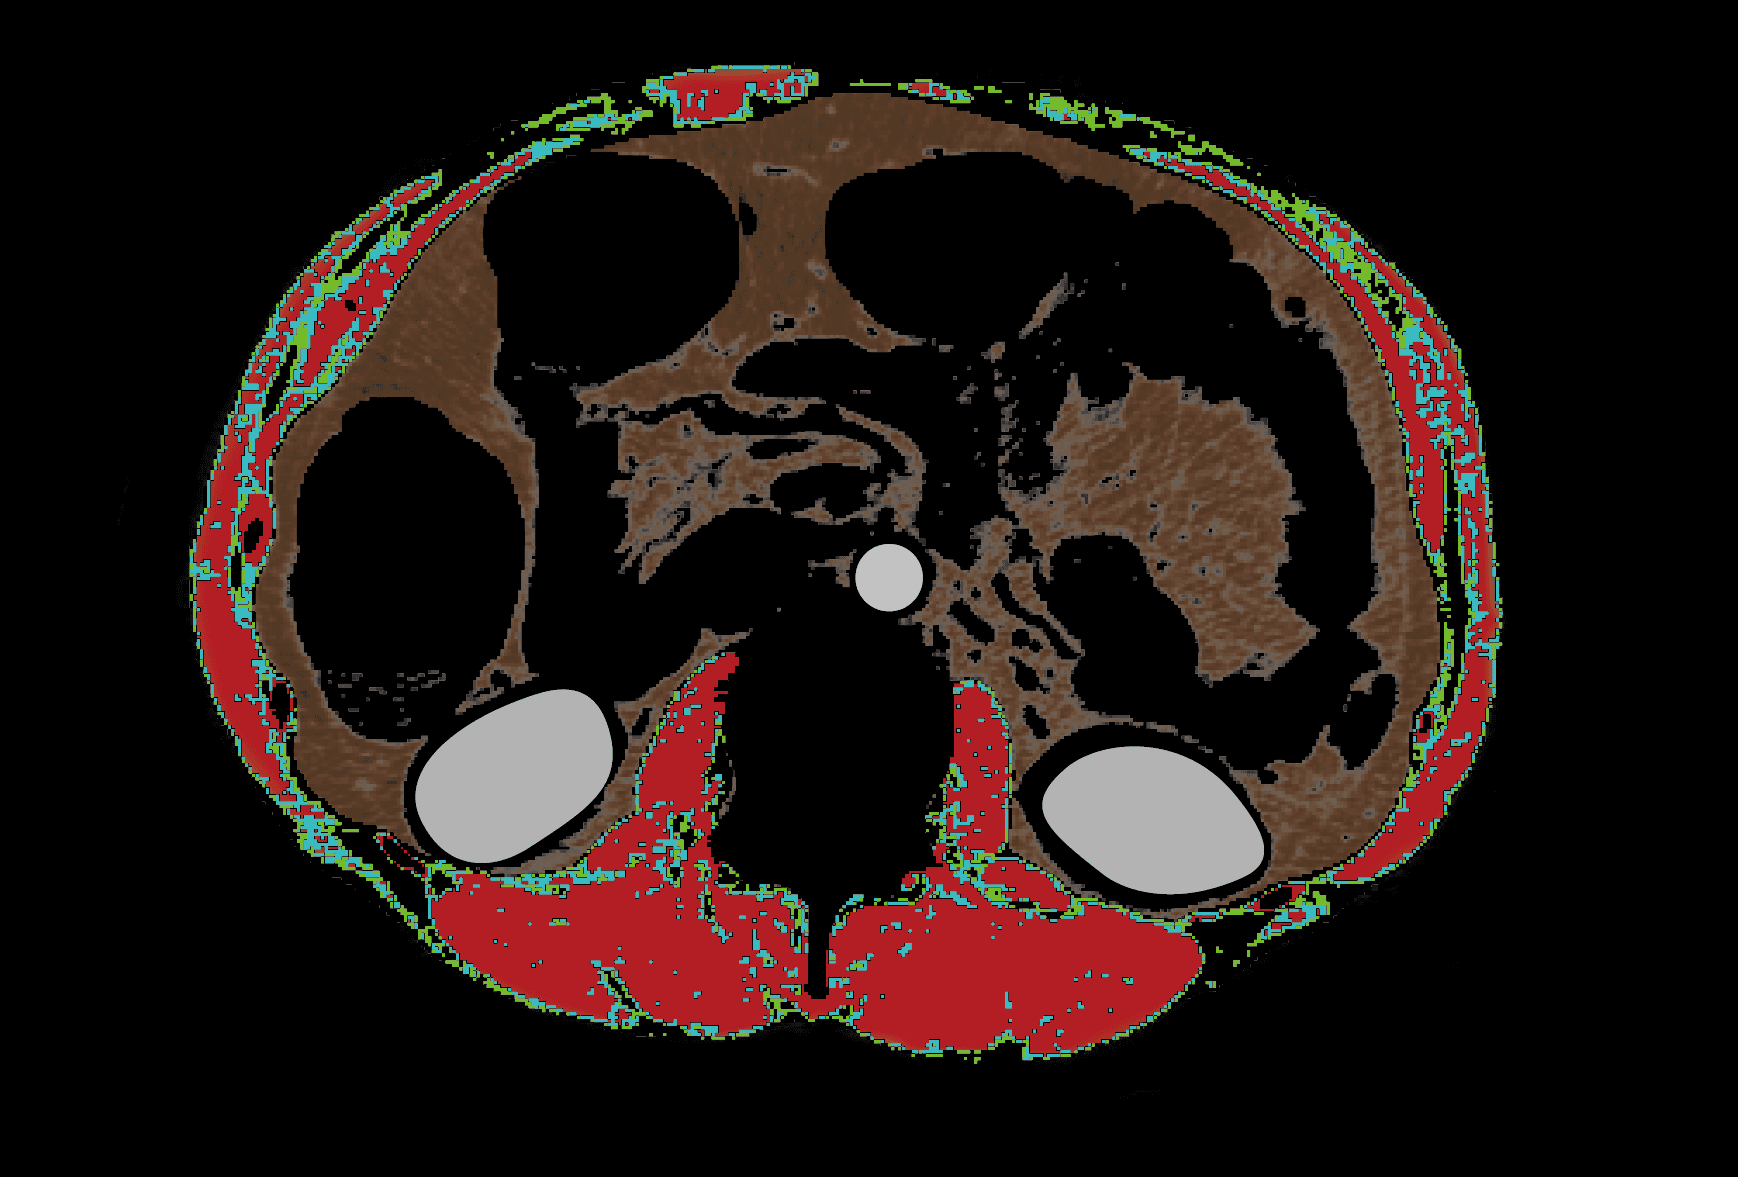

복부둘레근육 분할 성능 96%

우수한 일치도 입증

프로메디우스㈜. 성능 테스트 보고서 (PROS CT-01), 문서번호: PROS-Fuchsia-SPR, 제정일: 2023.05.16, 개정일: 2024.05.10, Rev.1.

NAMA, LAMA, IMAT가 무엇인가요? ¹